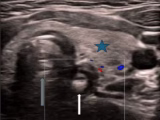

POCUS Diagnosis of Bacterial Lymphadenitis Later Determined to be Cat Scratch Disease: A Unique Presentation and Review

Alec P. Tolentino; Stanley Wojtas,; Camille D. Audette; Erin J. Meyer; Zachary W. Binder - This study presents a case of a teenage male evaluated in the pediatric emergency department for acute bilateral inguinal swelling, in which POCUS identified lymphadenopathy and guided the evaluation of a presumed infectious process, ultimately determined to be caused by [...]